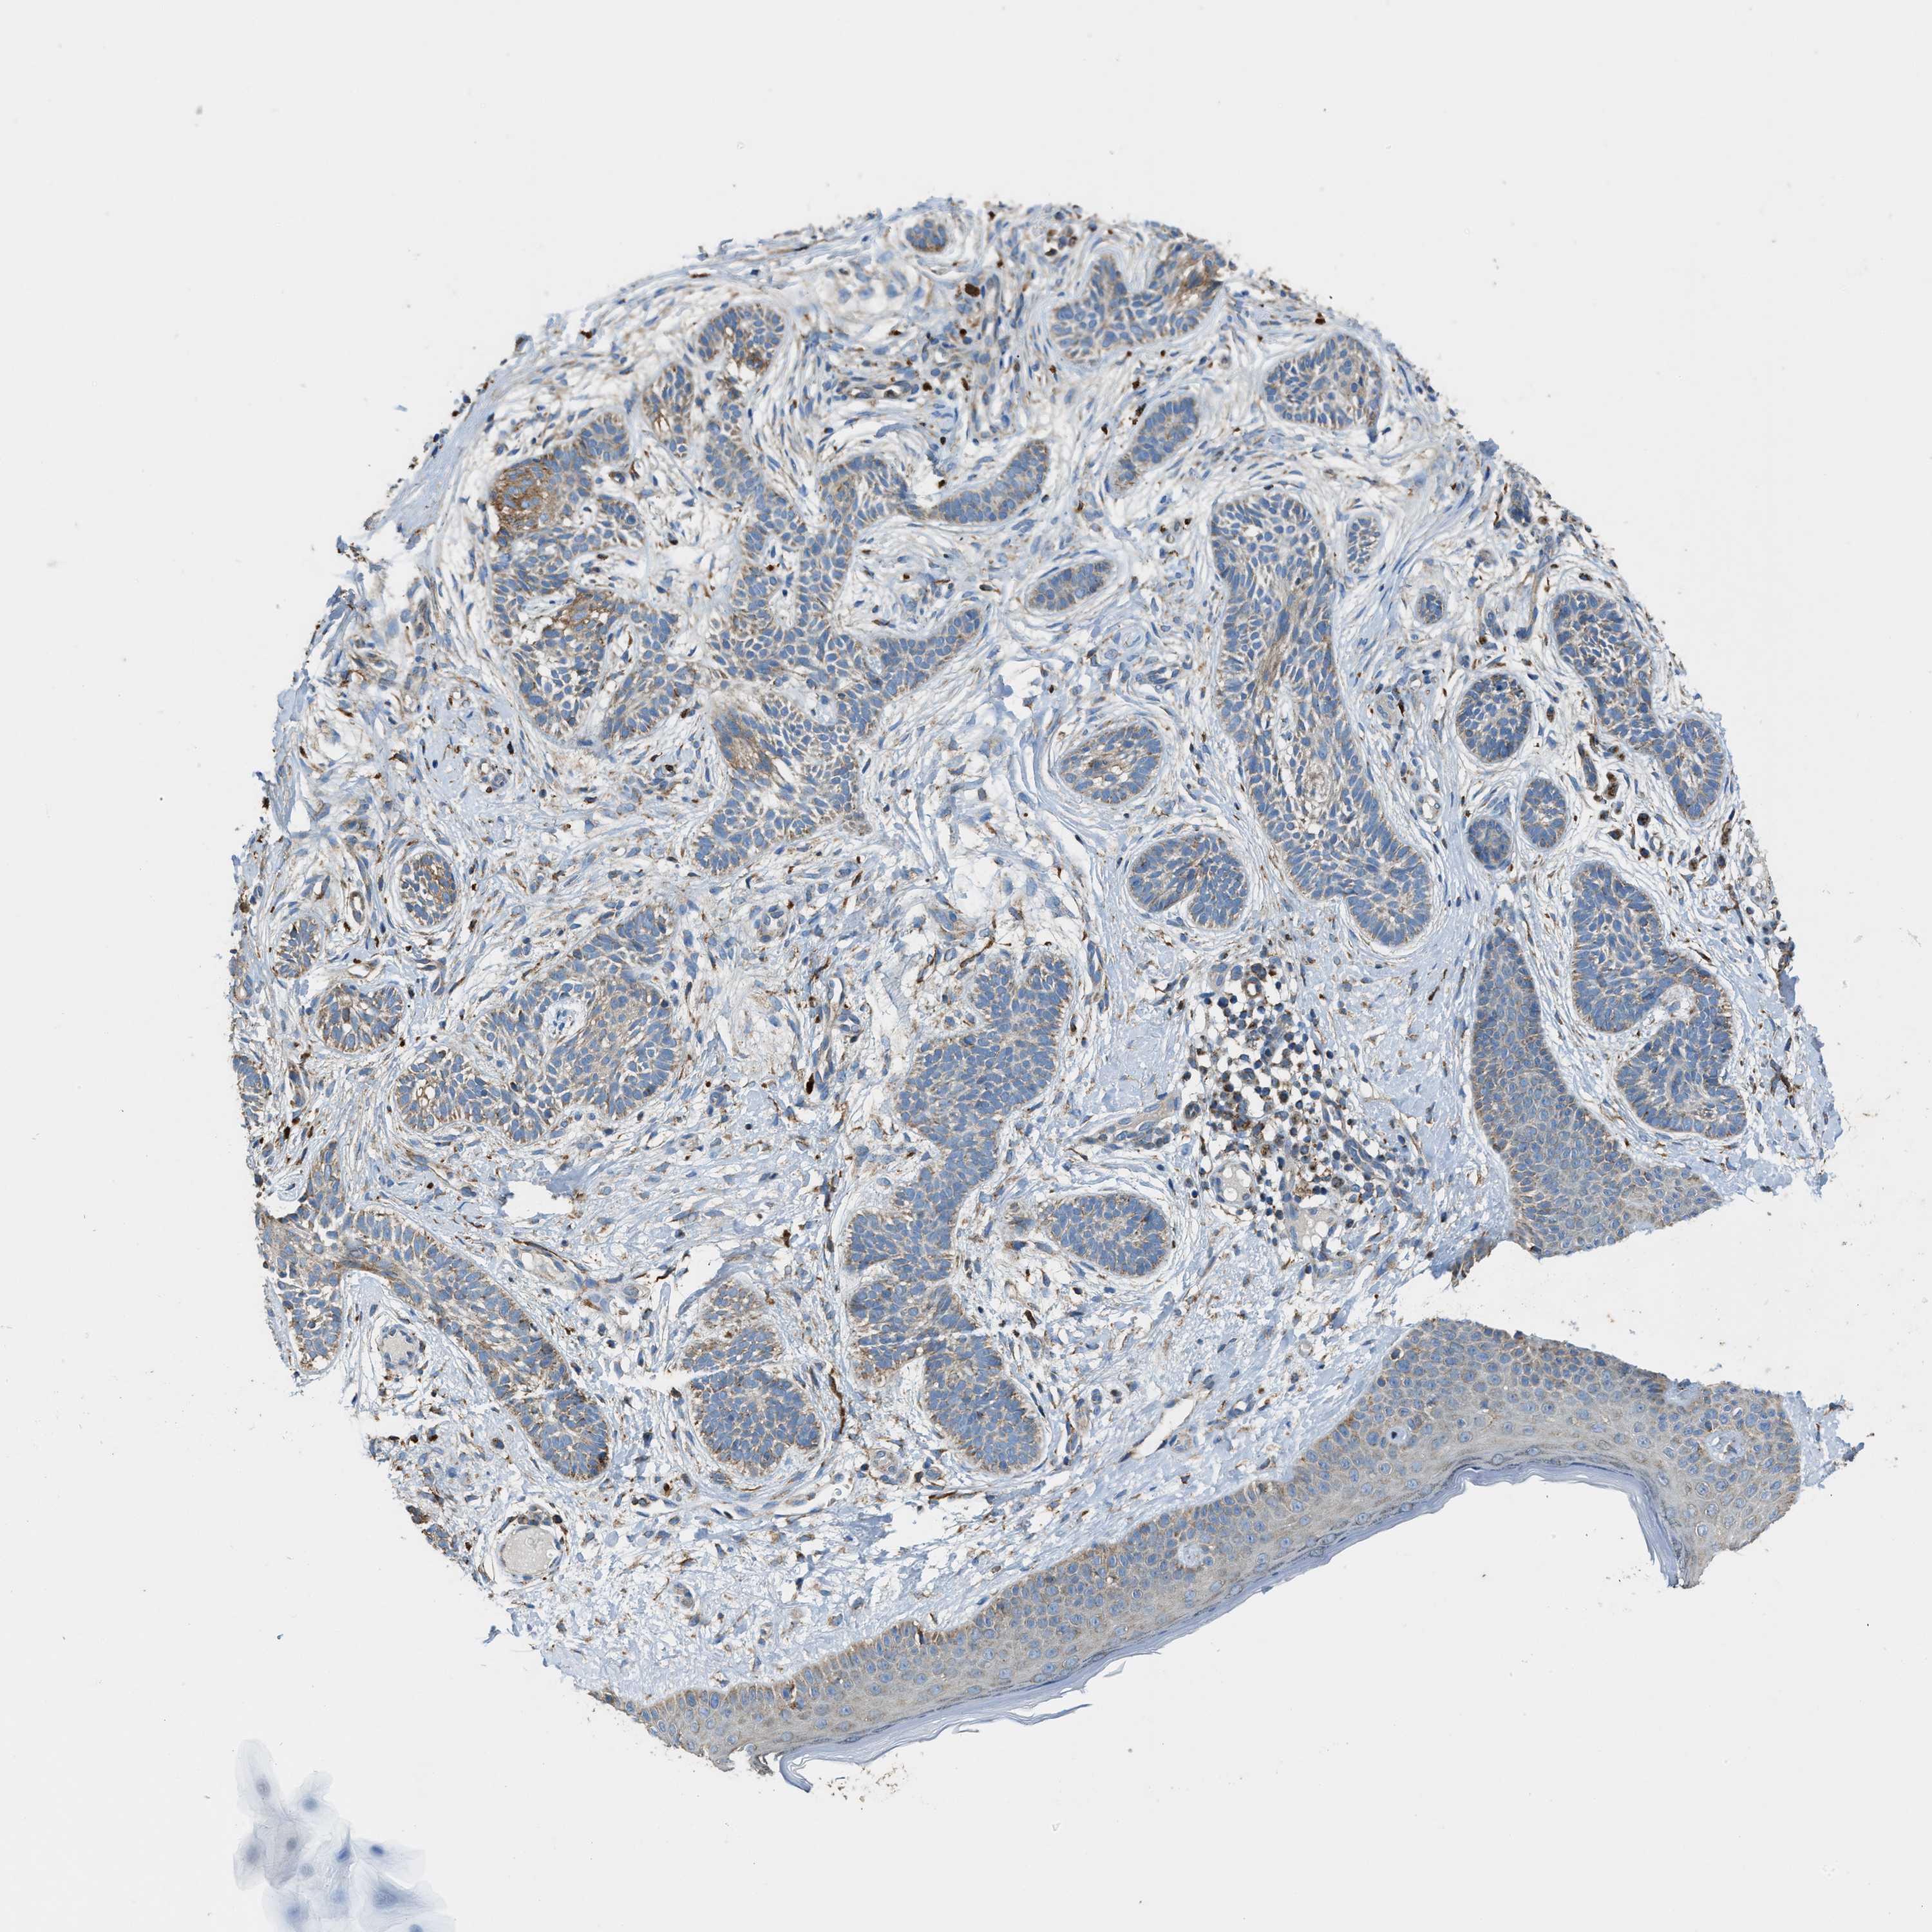

Basal cell and squamous cell cancer

SKIN CANCER - Protein expressioni

A mouse-over function shows sample information and annotation data. Click on an image to view it in a full screen mode. Samples can be filtered based on level of antibody staining by selecting one or several of the following categories: high, medium, low and not detected. The assay and annotation is described here.

Antibody stainingi

Antibody staining in the annotated cell types in the current human tissue is reported as not detected, low, medium, or high, based on conventional immunohistochemistry profiling in selected tissues. This score is based on the combination of the staining intensity and fraction of stained cells.

Each image is clickable and will lead to virtual microscopy that enables deeper exploration of all samples and also displays staining intensity scores, fraction scores and subcellular localization as well as patient and tissue information for each sample.

Antibody HPA021167

Staining

High

Medium

Low

Not detected

Intensity

Strong

Moderate

Weak

Negative

Quantity

>75%

75%-25%

<25%

None

Location

Nuclear

Cytoplasmic/membranous

Cytoplasmic/membranous,nuclear

Squamous cell carcinoma, NOS